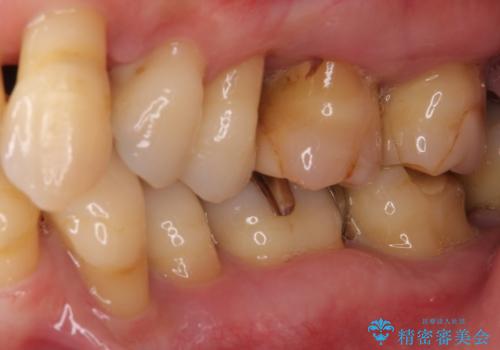

- 近医に通い続けるも、一向に不快感が改善しないとのことで来院された患者様です。

診察を行ったところ、重度歯周病の状態の上に上下の歯列が著しい叢生という状態でした。

歯周初期治療として抜歯や歯槽骨再生治療を行い、さらに歯周ポケット除去を行った後に矯正治療で歯列を整えて行くこととしました。